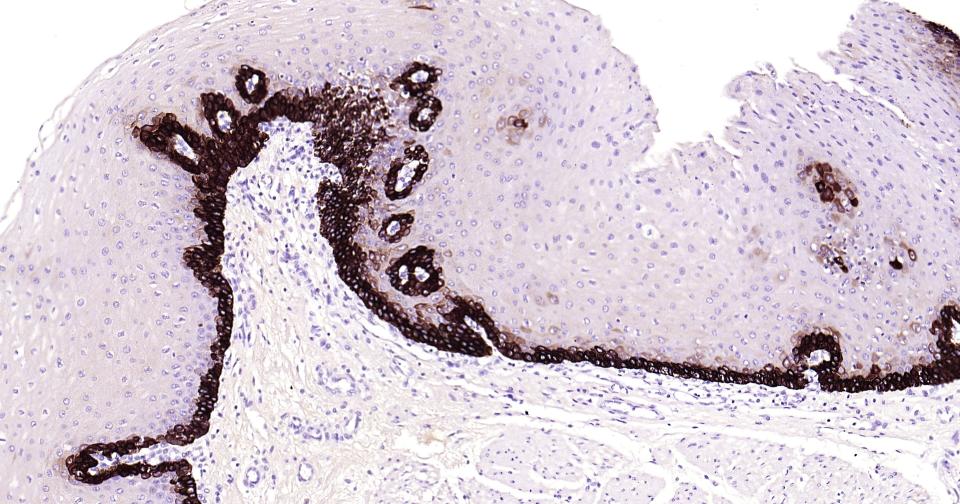

Paraformaldehyde-fixed, paraffin embedded Human Tonsil; Antigen retrieval by boiling in sodium citrate buffer (pH6.0) for 15 min; Antibody incubation with Cytokeratin 14? Monoclonal Antibody, Unconjugated(bsm-52054R) at 1:200 overnight at 4°C, followed by conjugation to the bs-0295G-HRP and DAB (C-0010) staining.

Paraformaldehyde-fixed, paraffin embedded Human Cervical Cancer; Antigen retrieval by boiling in sodium citrate buffer (pH6.0) for 15 min; Antibody incubation with Cytokeratin 14? Monoclonal Antibody, Unconjugated(bsm-52054R) at 1:200 overnight at 4°C, followed by conjugation to the bs-0295G-HRP and DAB (C-0010) staining.